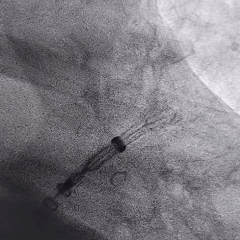

术中封堵器展开过程

鞘管定位

展开过程